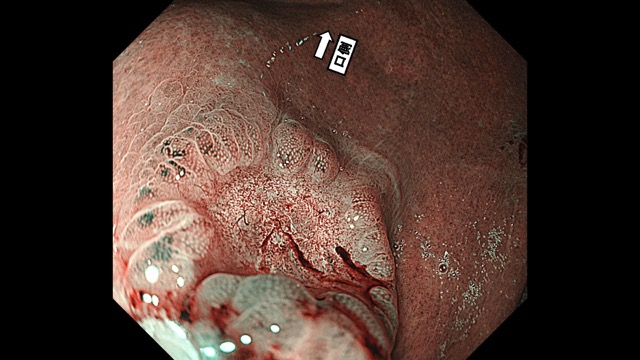

胃012